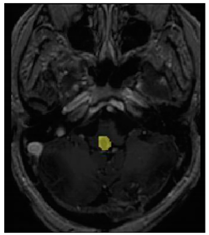

Three cases from the NTUH dataset showing representative results of different models were shown in Table 2, Table 3 and Table 4. The overall dice scores of these networks on the NTUH dataset ranged from 0.33 (DeepMedic) to 0.51 (V-Net). Table 5 shows the detailed performance of each network tested with the NTUH dataset.

Table 4.

Predictions with high dice scores.